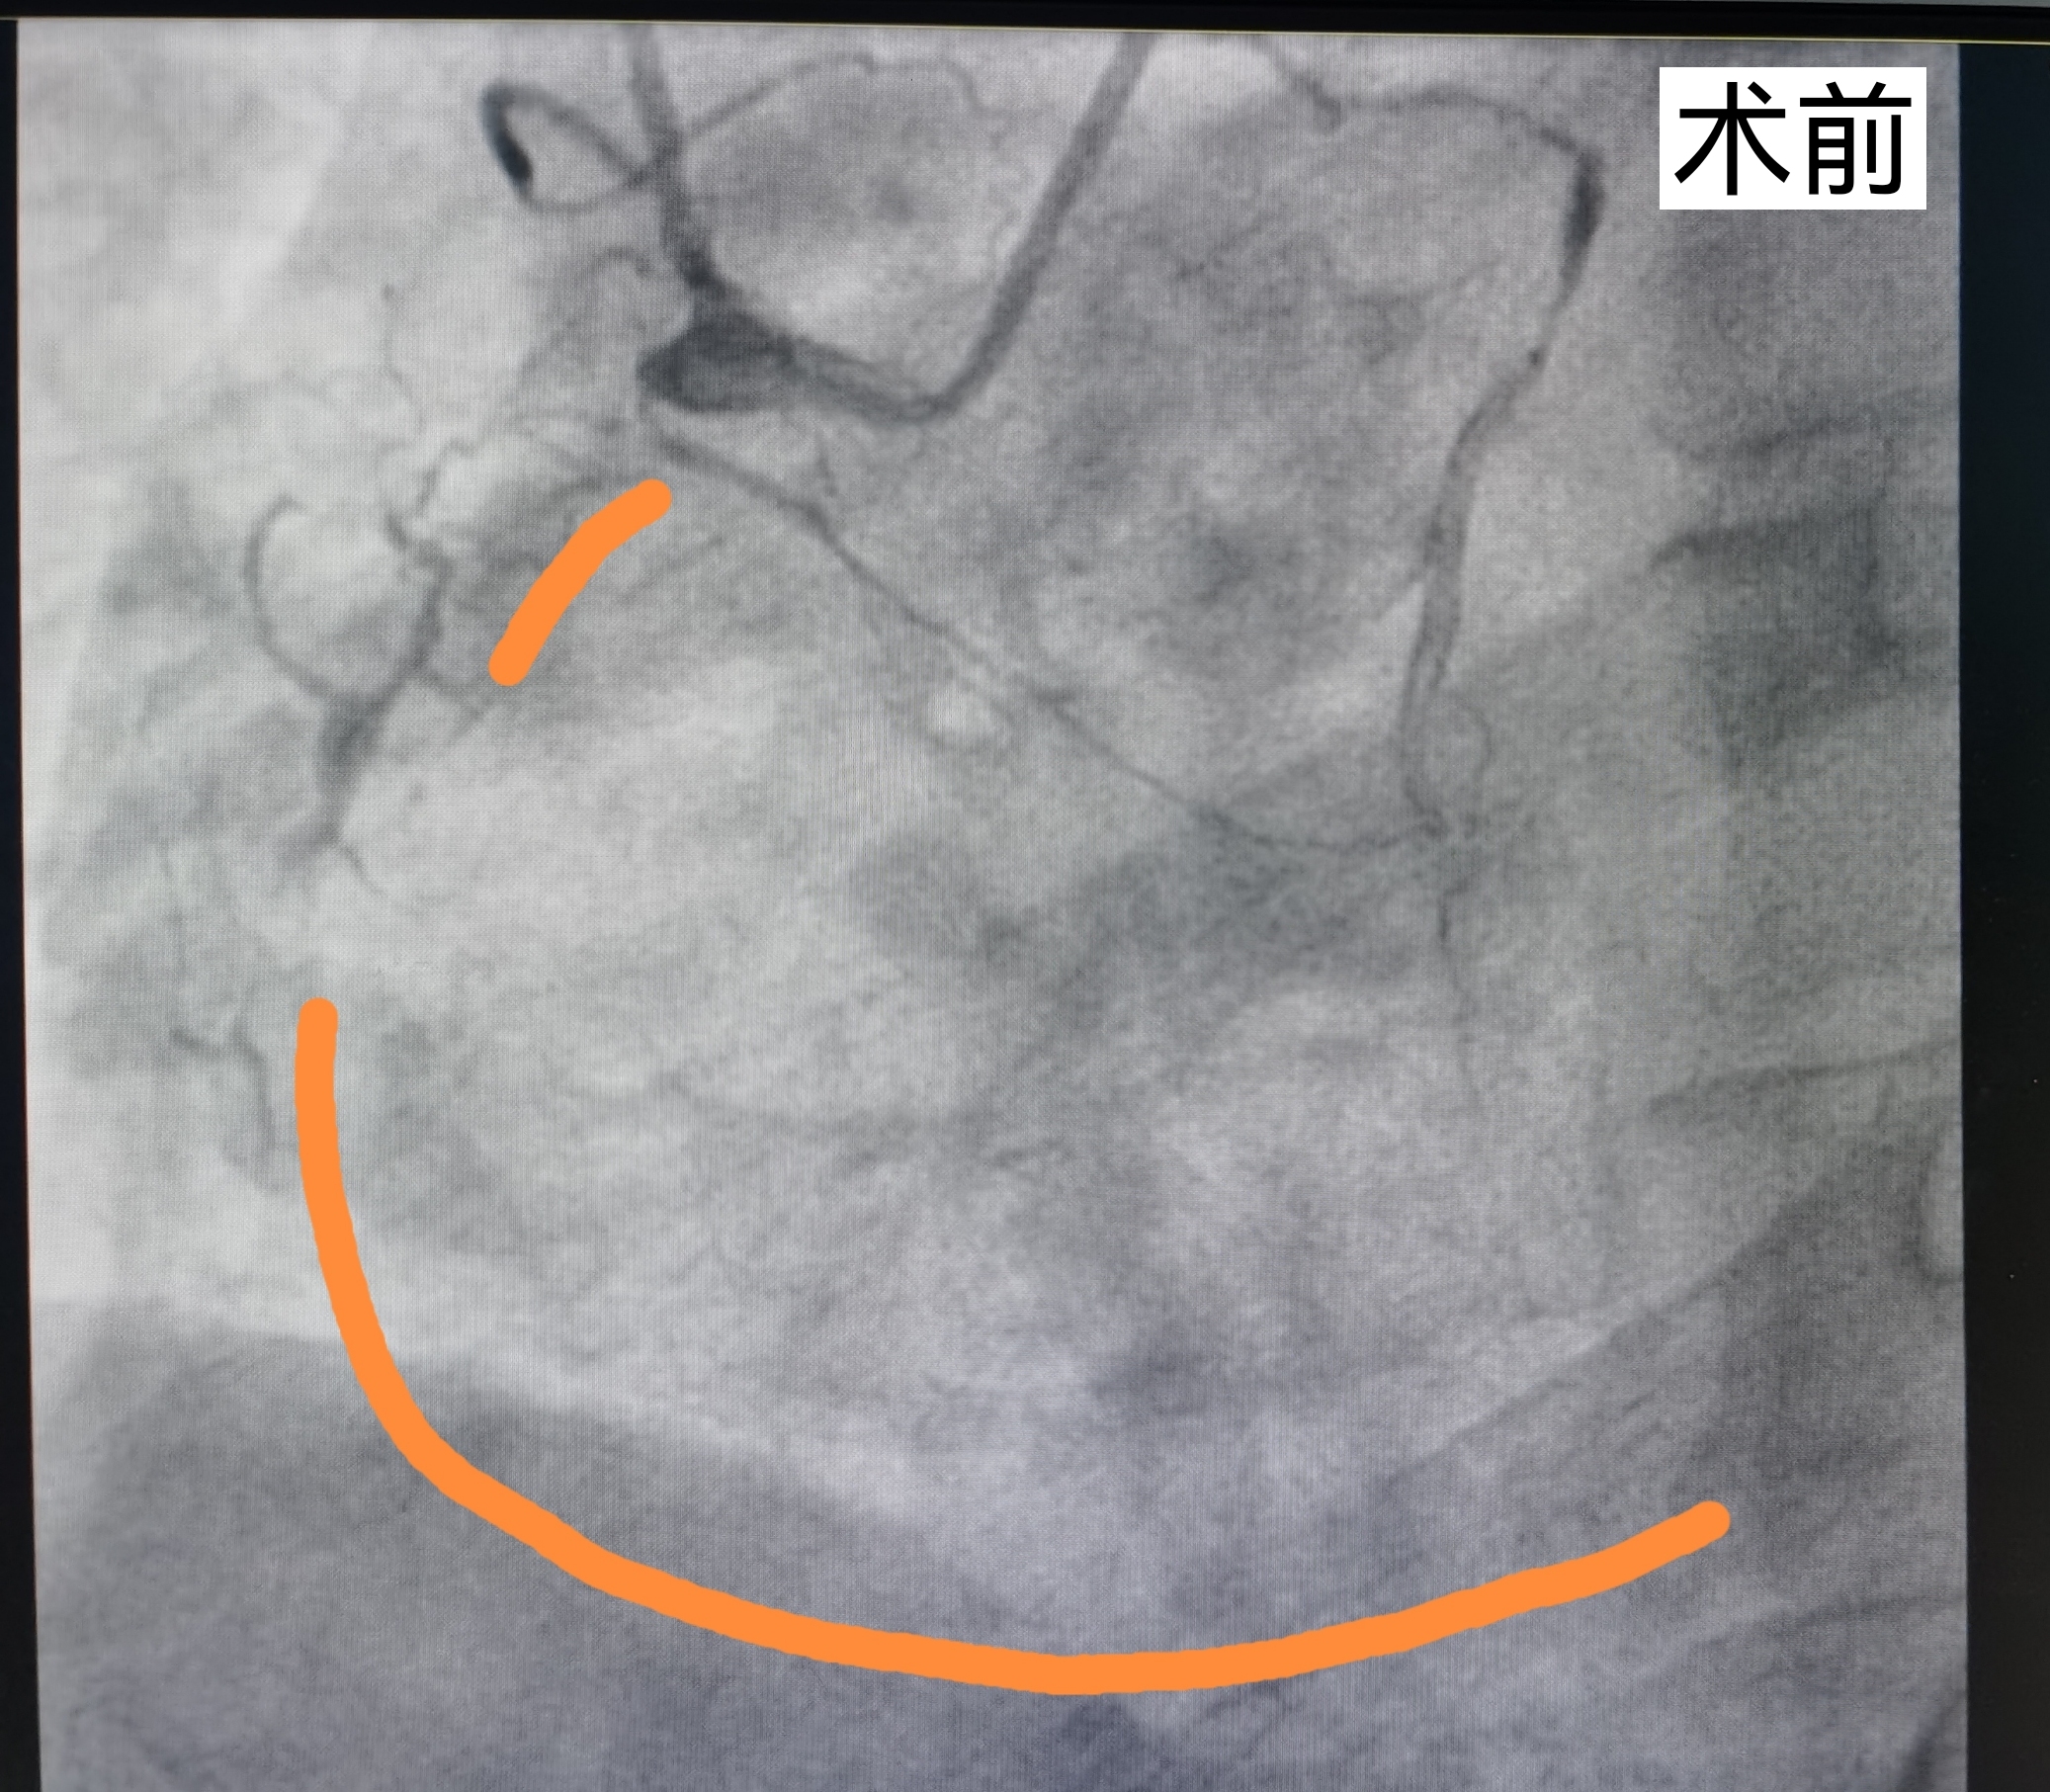

术前右冠脉血管几乎无血流,黄色部分为手绘的模拟血管示意图。

8月18日,范先生接受第二次手术,准备开通完全闭塞的右冠脉血管,该血管共有三处闭塞,并且有明显钙化。手术进行了7个小时,潘宏伟主任带领团队克服一次次的艰难险阻,不断尝试,终于成功开通血管,植入支架。